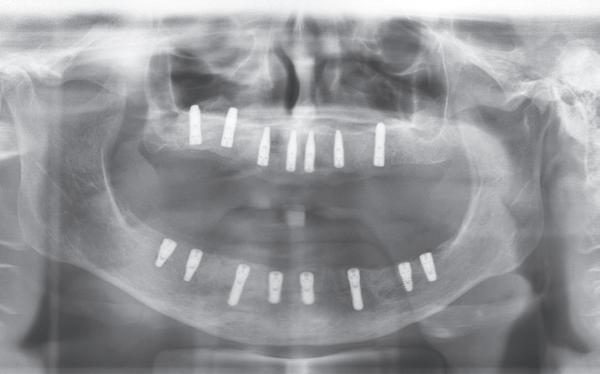

7. OPT na abutmentchirurgie 6 maanden later. De integratie van de implantaten met de botopbouw & sinusliften verloopt voorspoedig.

In de prothetische fase (zie foto’s) is in de bovenkaak gebruikgemaakt van verschroefde zirconia bruggen, die enkel buccaal zijn opgebakken. Deze bruggen zijn verlijmd op individuele, geanguleerde titanium abutments. In de onderkaak is een verschroefde kunststofbrug op een titaniumbasis (wrap-around) gemaakt. Voor deze combinatie is gekozen vanwege een minder hinderlijk tikkend geluid bij functie en kleinere kans op breuk van de keramiek. Een nadeel is verhoogde slijtage van de kunststof elementen, maar deze zijn in de jaren later eenvoudig te vervangen op de bestaande brug. Ondanks alle digitale mogelijkheden is de afdruk en registratiefase analoog uitgevoerd, omdat in ervaring van de behandelaren dit bij deze totale rehabilitaties op implantaten nog altijd de grootste precisie oplevert. Er is afgedrukt met impregum in individuele lepels en de pasvorm is gecontroleerd met rigide duralay bars. De relatie wordt vastgelegd zoals bij een volledige prothese met waswallen en pijlpuntregistratie. De opstelling in was wordt gepast en laatste correcties worden gemaakt in samenspraak met de patiënt, de restauratieve tandarts en de tandtechnicus. Na het vastzetten van de suprastructuren worden de schroefgaten afgesloten met composiet.

in de zes maanden bij de mondhygiënist voor peri-implant reiniging, pocketmetingen, mondhygiëne instructies en controles. De AirFlow wordt daarbij standaard gebruikt. Verder wordt de patiënt na één, drie en zes jaar gezien voor controle van de suprastructuren door de restauratieve tandarts. Uit de röntgenfoto’s kan afgeleid worden dat het botniveau gelijk blijft over tijd. Klinisch ziet de situatie er infectievrij uit; de patiënt onderhoudt het zelf netjes met ragertjes, een elektrische tandenborstel als ook de Waterpik.